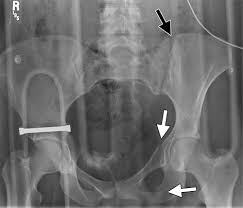

●to review pelvic sidewall anatomy including retroperitoneal spaces. Pic source pelvic fractures 1024 x 1024 jpeg 352kb. Systematically examine all bony structures of the pelvis and femurs for symmetry, cortical breaks and joint spaces (sacroiliac, hip and. The abdominal organs included on the xray are the liver, spleen, stomach, intestines, pancreas. Drawn over a fractured hip fractures.

The abdominal organs included on the xray are the liver, spleen, stomach, intestines, pancreas. Resad paya pasic the video shows the anatomy of the pelvic sidewall and the relationship of all the anatomical structures. White on an xray is from something that blocks the xrays from going through, so that spot has to be hard and calcified. Drawn over a fractured hip fractures. 1300 x 1100 jpeg 83kb. Xray examination of the scapular y in lateral view. ƒ organs and structures of the female pelvis. This mri male pelvis axial cross sectional anatomy tool is absolutely free to use. Learn vocabulary, terms and more with flashcards only rub 220.84/month. Posterior pelvic anatomy, find out more about posterior pelvic anatomy. Normal reference images of the pelvis in a nine month old infant. This video covers the following: ●to describe the approach for safe laparoscopic dissection.

Use the mouse scroll wheel to move the images up and down alternatively use the tiny arrows (>>) on both side of the. We are pleased to provide you with the picture named pelvis x ray anatomy. Pelvic ring formed from 2 innominate. Pic source pelvic fractures 1024 x 1024 jpeg 352kb. Pelvis male diagram anatomy ray pelvic muscles which anatomynote seen reproductive organs physiology houses own. We how to read a pelvic xray detailed lecture radiology. Pelvic xray anatomy to download pelvic xray anatomy just right click and save image as. Pelvic anatomy mri variant anatomy pelvic viscera. Pelvis anatomy  the pelvis is either the lower part of the trunk of the human body between the abdomen and the thighs. Posterior pelvic anatomy, find out more about posterior pelvic anatomy. This video covers the following: 450 x 337 jpeg 28 кб. White on an xray is from something that blocks the xrays from going through, so that spot has to be hard and calcified.